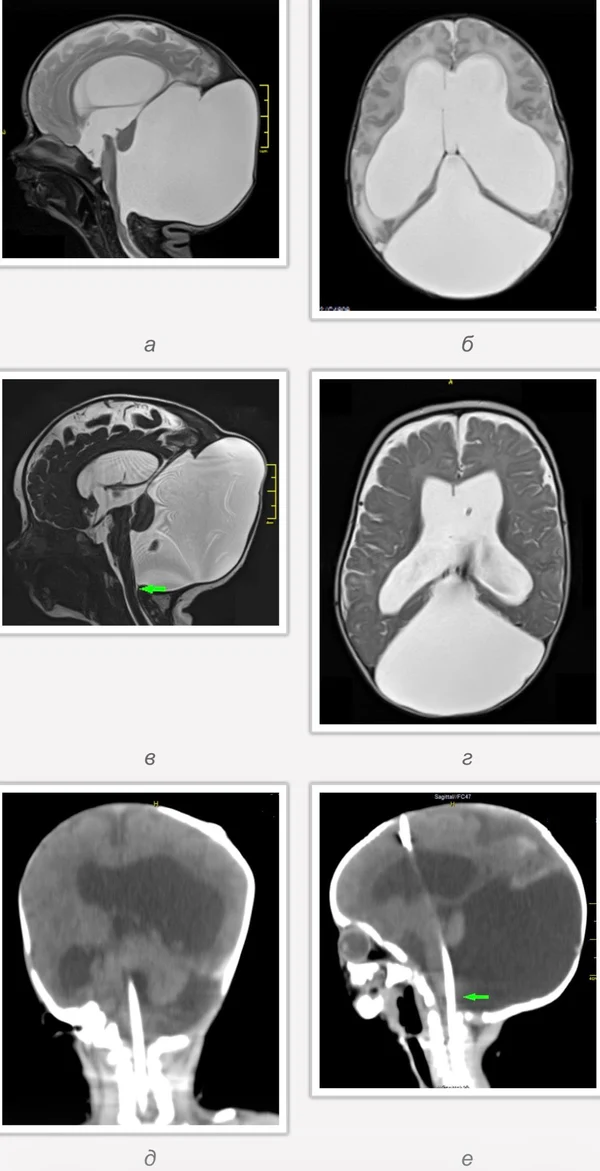

кисты, аномалии Денди-Уокера и др.Операции при внутричерепных кистах. В основном встречаются арахноидальные кисты различных локализаций и кисты сосудистых сплетений боковых желудочков. Пациентам с врождёнными кистами операции проводятся в следующих ситуациях: увеличении объема кисты в динамике, наличии клинических проявлений, компрессии и дислокации мозговых структур, наличии окклюзии ликворных путей. Нами используются 2 способа хирургического лечения кист: эндоскопическая перфорация стенок кист и открытая резекция кист. Открытая резекция кист проводится при ретроцеребеллярных арахноидальных кистах (рис. 2), при арахноидальных кистах межполушарной щели при отсутствии непосредственного контакта их стенок со стенками расширенных желудочков головного мозга и повторного увеличения кист средней черепной ямки после эндоскопической кисто-цистерностомии. Техника операции заключается в проведение краниотомии и максимальном иссечении стенок кист с созданием широкого сообщения кист с субарахноидальным пространством. Эндоскопические операции проводятся при арахноидальных кистах межножковой и пинеальной цистерн, арахноидальных кистах межполушарной щели при тесном контакте их стенок со стенками расширенной желудочковой системы (рис. 3), первично при арахноидальных кистах средней черепной ямки, а также при кистах сосудистых сплетений боковых желудочков. При арахноидальных кистах межножковой цистерны эндоскопически проводится перфорация стенок кисты, сообщая ее с просветом III желудочка и межножковой цистерной – эндоскопическая вентрикуло-кисто-цистерностомия (рис. 4). При арахноидальных кистах пинеальной цистерны проводится перфорация кисты в передне-верхних её отделах с созданием сообщения полости кисты с просветом III желудочка – эндоскопическая кисто-вентрикулостомия. С целью предотвращения облитерации сформированного отверстия иногда в полость кисты под контролем эндоскопа вводится стент перфорированный на протяжении (рис. 5, 6). Эндоскопическая кисто-цистерностомия выполняется при арахноидальных кистах средней черепной ямки. При этом создается широкое сообщение кисты с базальными цистернами. При кистах сосудистых сплетений боковых желудочков проводится их вскрытие в просвет боковых желудочков – эндоскопическая кисто-вентрикулостомия. При множественных кистах проводится их хирургическое сообщение между собой – интеркистосмия